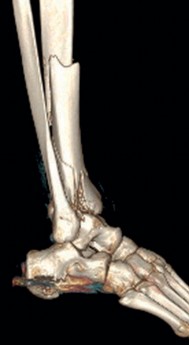

Pre-operative planning is the cornerstone of successful execution in complex pilon-variant tibial shaft fractures. The surgeon must transition from a conceptual understanding of the injury to a concrete, step-by-step surgical blueprint. This begins with high-quality orthogonal radiographs of the entire tibia, ankle, and knee. However, plain films drastically underestimate the degree of articular comminution and central impaction. A fine-cut computed tomography (CT) scan with 2D multiplanar reformats (coronal and sagittal) and 3D surface rendering is absolutely mandatory.

The CT scan allows the surgeon to map the fracture lines, identify the primary articular fragments (Chaput, Volkmann, medial malleolus), and quantify the degree of central die-punch impaction. In an AO/OTA 43C3.3 fracture, where no articular fragment is in continuity with the diaphysis, the surgeon must plan the sequence of reduction. Typically, the fibula is addressed first to restore lateral column length and rotation, provided the fibular fracture is not located at the level of the syndesmosis where fixation might interfere with the lateral surgical approach to the tibia.